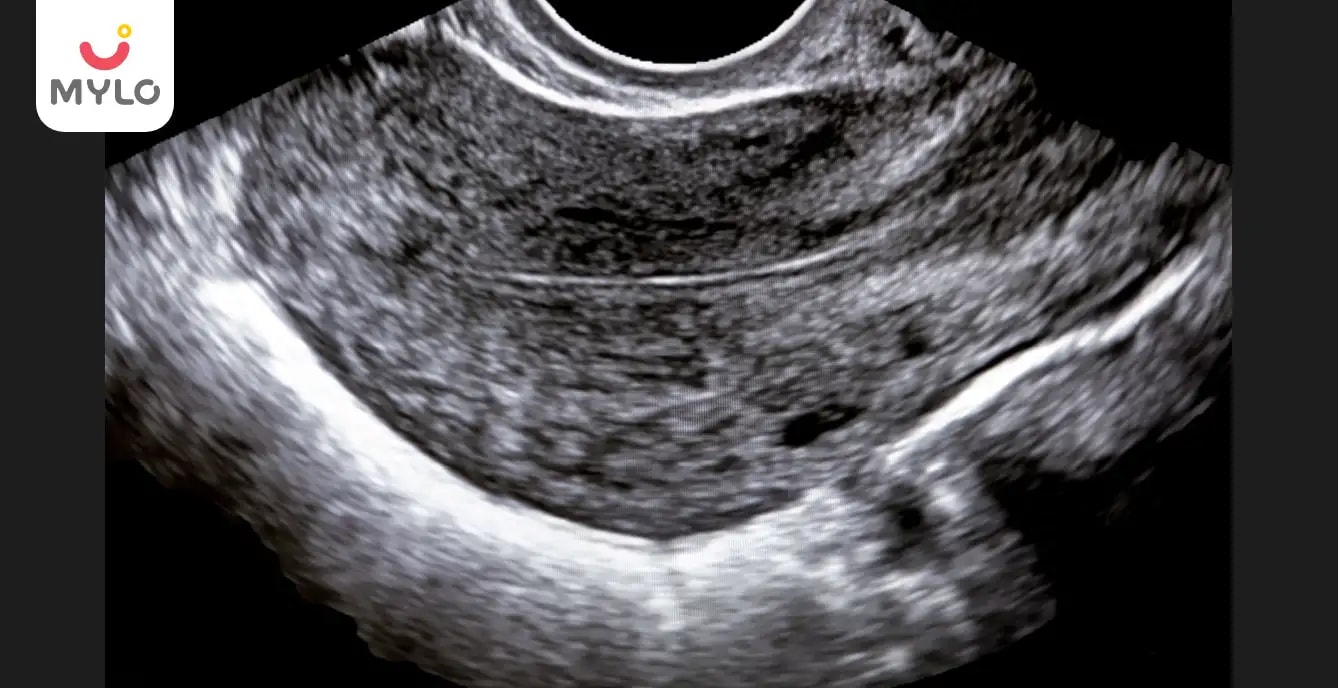

The endometrium typically becomes trilaminar during the fertile window, which occurs around the middle of the menstrual cycle and is characterized by a surge in estrogen levels. Monitoring the thickness and appearance of the endometrium through ultrasound scans can help determine if it has become trilaminar.